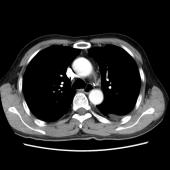

[影像描述]

左肺下叶可见高密度肿块影,边界清晰,边缘不规则,左肺下叶支气管局部截断,增强后病灶边缘轻度强化,中心未见明显强化;左侧胸腔内可见液性密度影;纵隔内未见明确肿大淋巴结影。